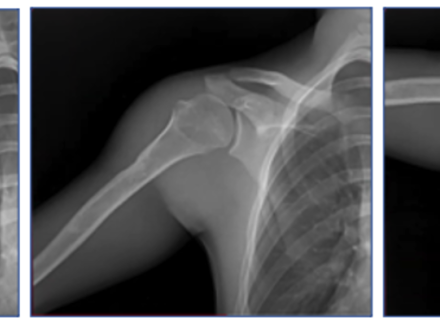

DDR is a novel, low-dose X-ray imaging technique available on Konica Minolta Healthcare DR Systems that captures both static images and cinegrams, providing an innovative way to obtain detailed images of complex joints while in motion and observe physiological cycles. By acquiring a series of images at high speed, DDR generates a cineloop that enables clinicians to visualize anatomical motion over time (cineradiography), enhancing the system’s diagnostic capabilities. Studies have demonstrated the clinical utility of DDR in pulmonary medicine, orthopedics and other specialized applications such as swallow studies or post-bariatric sleeve assessments.